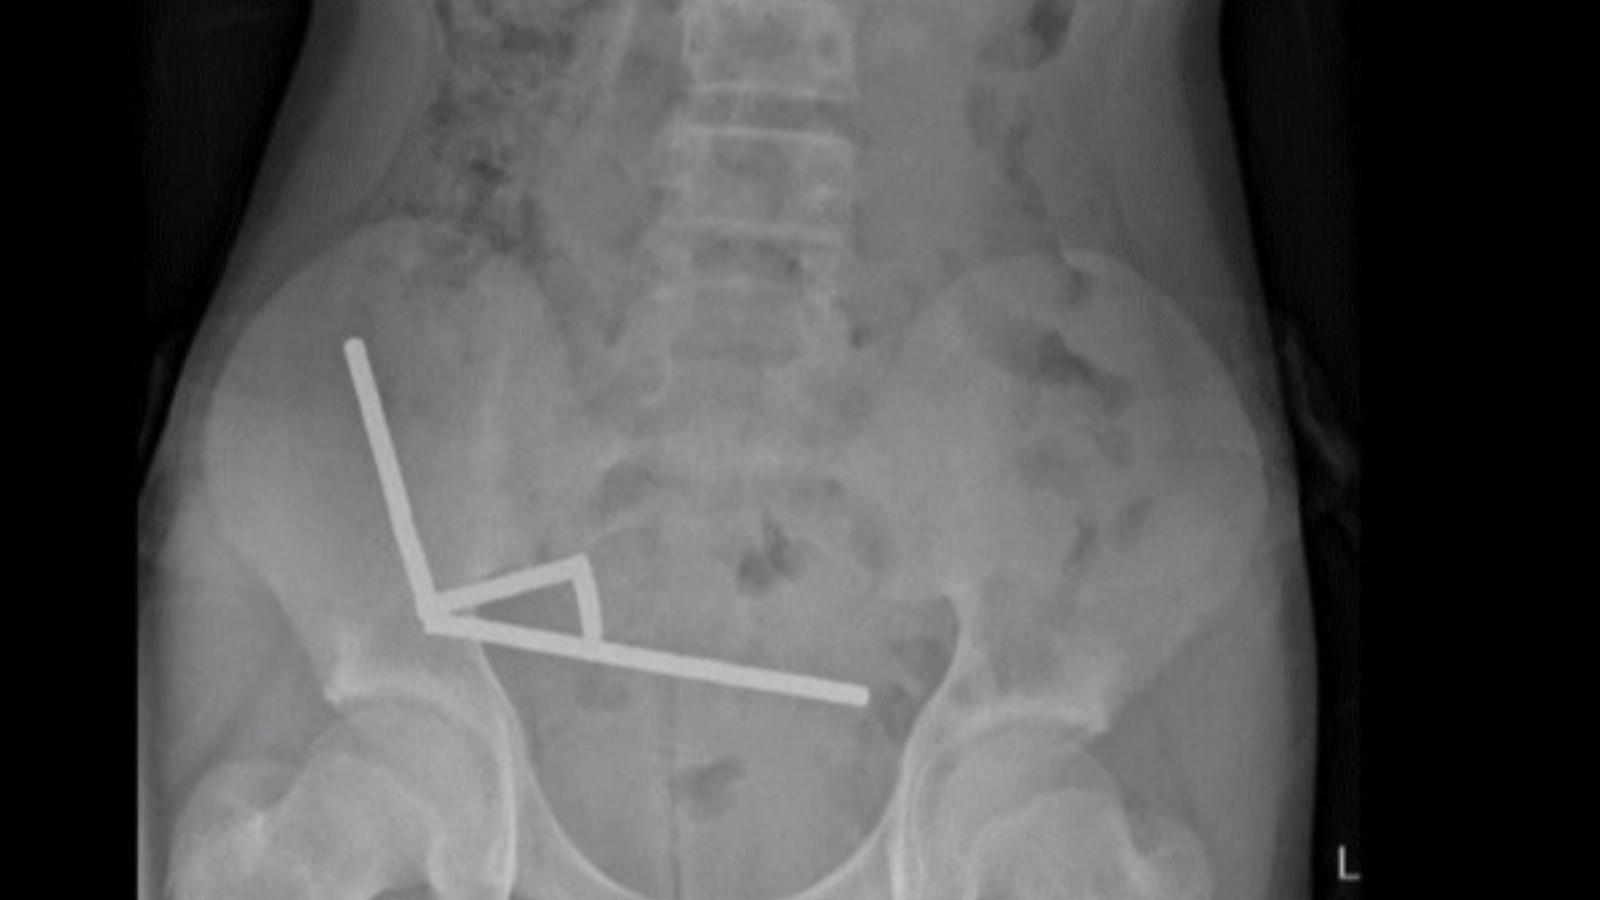

A fiút erős hasi fájdalmakkal vitték be a Tauranga kórházba, ahol saját bevallása szerint egy héttel korábban körülbelül 100 neodímium-mágnest nyelhetett le. A hasüregéből kivett apró fémtárgyak száma azonban végül ennél jóval több volt. A röntgenfelvétel négy különálló mágnesláncot mutatott ki a belei különböző szakaszaiban, miután azok a testében összetapadtak, ami szövetelhalást okozott.